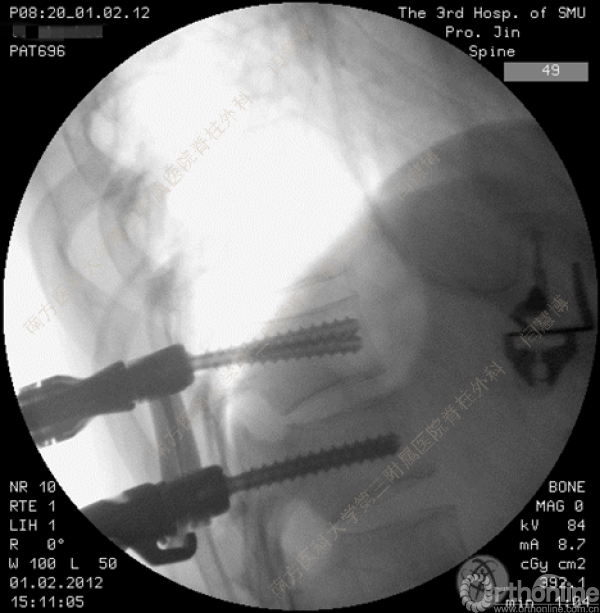

胸腰椎骨折是指由于外力造成胸腰椎骨质连续性的破坏,在如车祸、高处坠落等意外事故中,是最常见的脊柱损伤。老年患者由于本身存在骨质疏松,甚至有可能因为一些如滑倒、跌倒等低暴力因素导致胸腰椎骨折。胸腰椎骨折患者常合并神经功能损伤,且由于致伤因素基本为高能损伤,常合并其他脏器损伤,这为治疗带来了极大的困难和挑战。针对胸腰椎骨折,南方医科大学第三附属医院闫慧博教授介绍了他们运用微创方法治疗的经验。